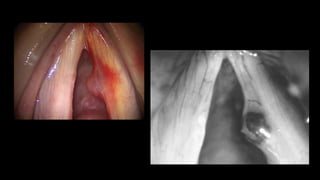

EXCISION OF MUCUS RETENTION CYST

INTRACORDAL CYSTS • Classifiedas either mucus retention cysts or epidermoid inclusion cysts •PATHOPHYSIOLOGY- • MUCUS RETENTION CYST- arise when the duct of a mucus gland becomes plugged and glandular secretions •EPIERMOID INCLUSION CYST- contain accumulated keratin Healing of injured mucosa Epithelial cell rests in subepithelial layer

• 54.

CLINICAL FEATURES •Voice abuse-in epidermoid cyst •Husky, breathy or harsh voice •Mucus retention cyst- less vocal limitations •Originate just below the free margin of the vocal fold with medial projection •Stroboscopy- mucosa overlying cysts stops vibrating before mucosa surrounding the cyst

• 56.

• 57.

MANAGEMENT •SURGICAL- •Small shallow incisionis made on the fold’s superior surface. •Careful dissection reveals the cyst •Excision of the cyst free of the mucosa and vocal ligament •SPEECH THERAPY

• 58.

EXCISION OF MUCUSRETENTION CYST